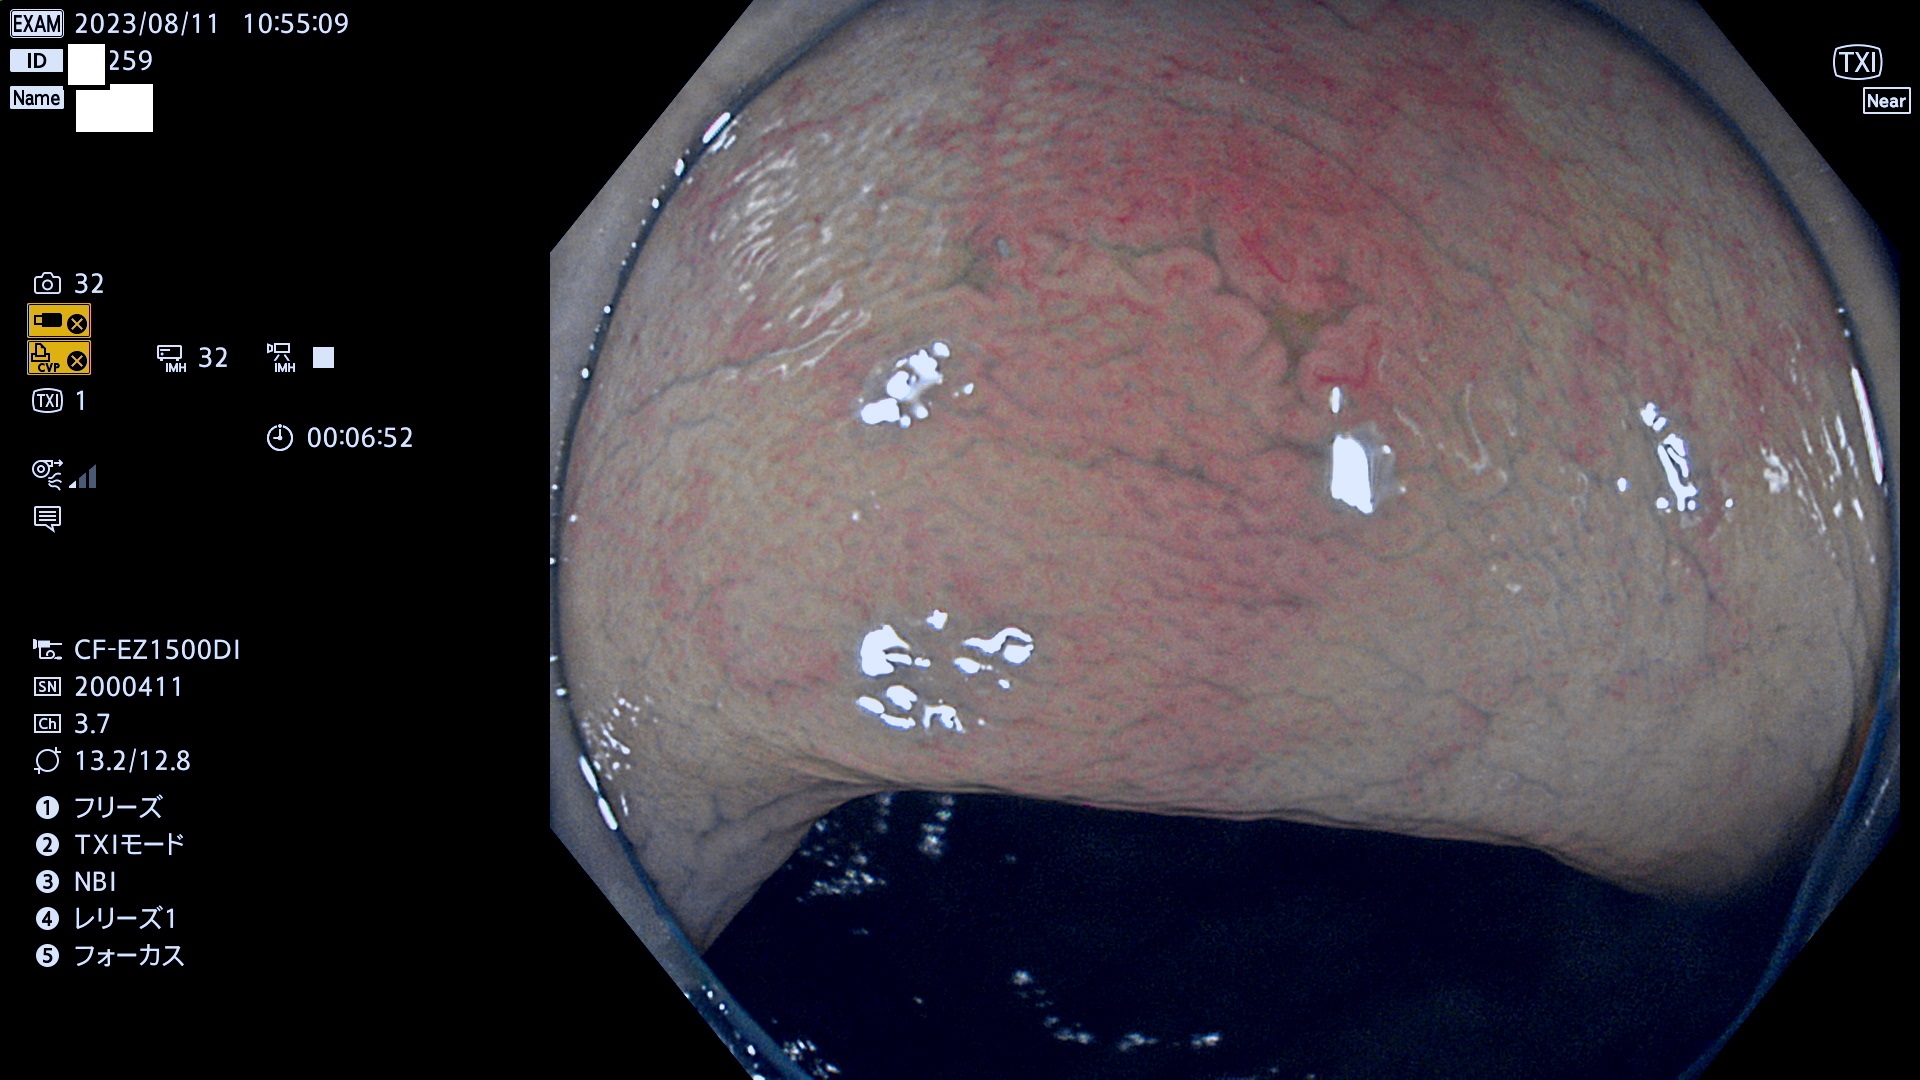

表面型腺腫(Flat Adenoma)の中で、完全に平坦な物をUb、陥凹している物をUcと呼びます。平坦隆起型(Ua)よりも、発見が難しく危険な病変です。このタイプは「内視鏡後・大腸癌の重要犯人」であり、この発見率は「腺腫発見率」よりも、重要な意味があります。

毎週の検査(木・金・土・日)に発見されたUb、Uc型・腺腫を、その週の日曜の夜にUPし1週間、提示します。

抽出の対象期間 2023年8月10日(木)〜8月13(日)の4日間(48件の検査)11件